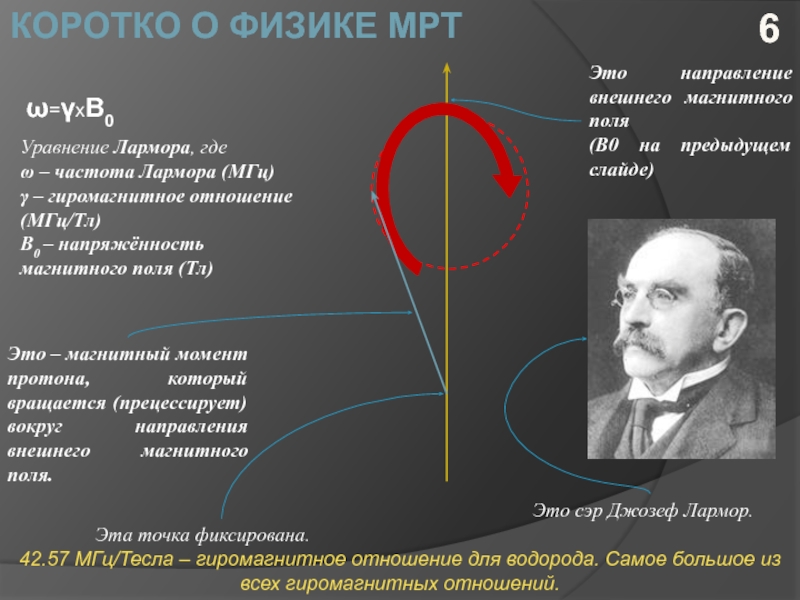

Ларморова Прецессия и Магнитный Момент

Раздел: Картинки на заметку